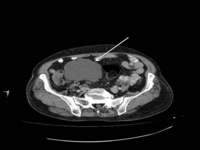

Yoğun içerikli kistik lezyonlar, genellikle çeşitli organlarda görülen, sıvı veya yarı sıvı içerik barındıran ve belirli bir kapsül ile çevrili olan anormal oluşumlardır. Bu lezyonlar, içerdikleri maddelerin yoğunluğuna göre sınıflandırılabilir ve farklı patolojik durumların göstergesi olabilir. Bu makalede, yoğun içerikli kistik lezyonların özellikleri, tanı yöntemleri ve klinik önemi detaylı bir şekilde ele alınacaktır. 1. Yoğun İçerikli Kistik Lezyonların TanımıYoğun içerikli kistik lezyonlar, içerdikleri sıvının yoğunluğu yüksek olan ve genellikle bir kapsül ile çevrili kistlere verilen isimdir. Bu lezyonlar, sıvıların yanı sıra, bazen katı parçacıkları da içerebilir. Kistik lezyonlar, genellikle benign (iyi huylu) veya malign (kötü huylu) özellikler gösterebilir. 2. Yoğun İçerikli Kistik Lezyonların NedenleriYoğun içerikli kistik lezyonların oluşumuna neden olan faktörler arasında şunlar yer alır:

Bu belirtiler, lezyonun yerleşim yeri ve büyüklüğüne göre değişiklik gösterebilir. 4. Tanı YöntemleriYoğun içerikli kistik lezyonların tanısı, çeşitli görüntüleme yöntemleri ve biyopsi ile yapılabilir. Kullanılan başlıca tanı yöntemleri şunlardır:

Tanı Yöntemleri: Ultrasonografi ve manyetik rezonans görüntüleme (MRG) gibi tanı yöntemlerinin etkili olduğunu deneyimlemiş olmanız, bu süreçte ne kadar önemli bir yere sahip olduklarını gösteriyor. Bu yöntemler, lezyonların doğru bir şekilde değerlendirilmesi için kritik öneme sahiptir.